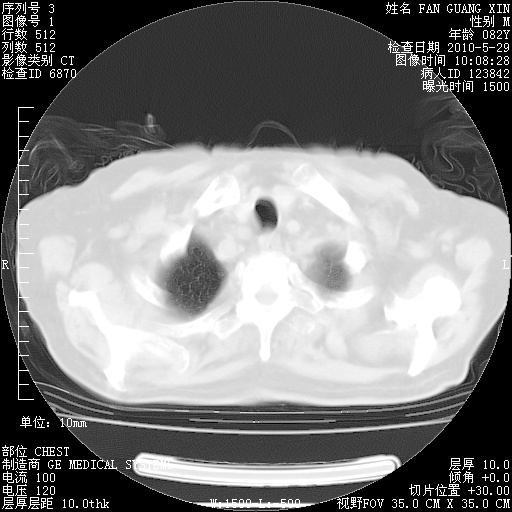

再治疗10天后的肺部CT 纵膈窗

从白细胞总数和中性比例看好像合并感染。肺部纹理好像比上次多,支气管炎?其他感染?

阅读此次胸部CT,肺间质渗出性改变较入院时有吸收。目前从体温、白细胞、中性分叶明显增高,肯定存在细菌感染(发生医院感染哦,若无消化道及泌尿系统等感染的依据,肺部感染可能大)。若你院头孢哌酮舒巴坦钠耐药率较高,同意你的方案,若48小时体温仍高,可考虑使用碳青霉稀类抗菌药物,同时可予超声雾化、注意滴数时加大液体量。白蛋白33.30g/L较低哦,需加强营养等支持治疗。